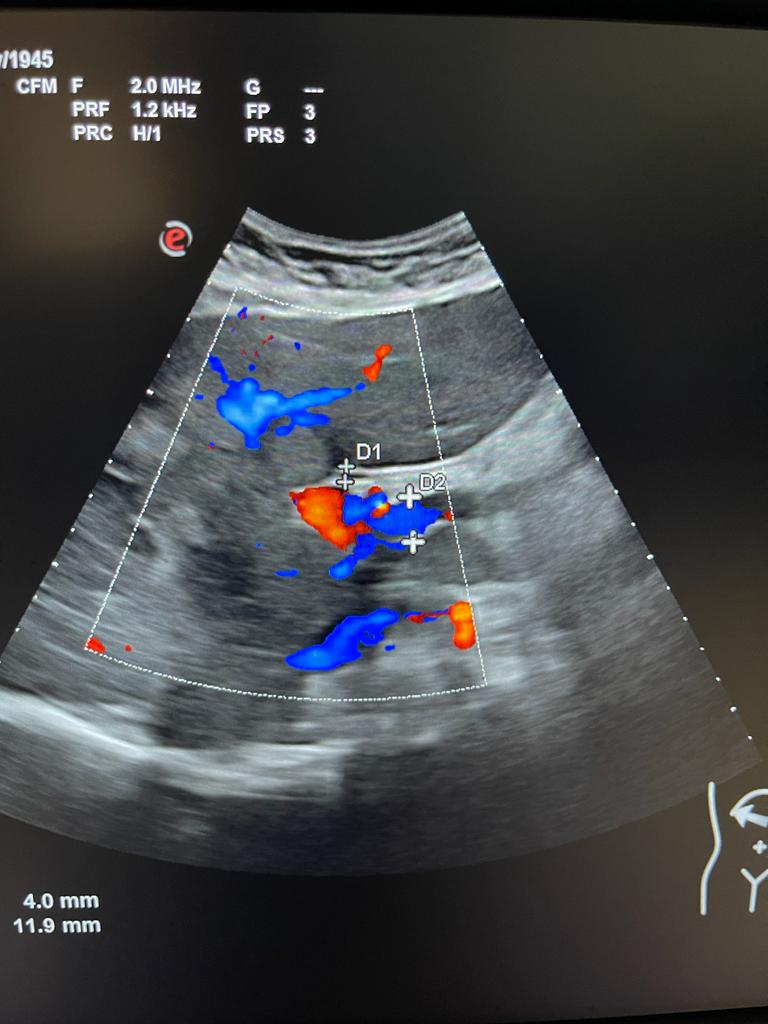

Se aprecia hígado heterogéneo con múltiples LOES hepáticas hiperecogénicas (una de ellas de unos 7x7 cm), sin captación de doppler. Al menos otras 2 LOES de menor tamaño presentan halo hipoecoico. Vesícula replecionada de contornos lisos y sin litiasis en su interior. Ambos riñones visualizados de tamaño normal y sin datos de hidronefrosis.